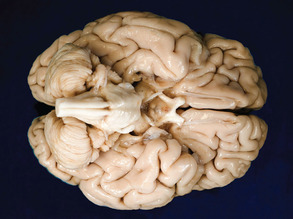

Rescuing Brain Cells